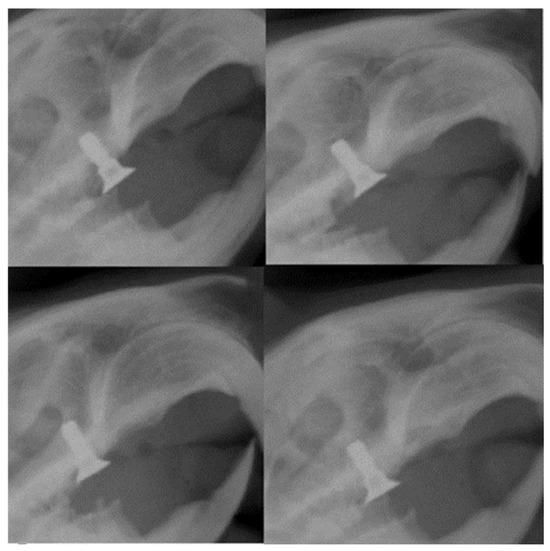

Radiological assessment is critical after implant placement, as the alveolar ridge’s height, width, and contour must be determined precisely. In the case of our study, the results showed an excellent fixation at the level of the alveolar ridge, the implant being in a parallel position with the remaining molars on the dental arch (Figure 14).

Figure 14. Radiographic images 30 days after placement of the implants in rats showing their parallel position with the rest of the teeth and the height concerning the dental plaque.